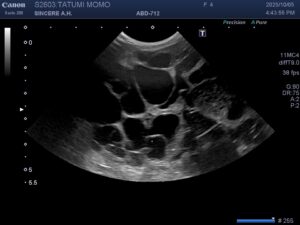

まだ若い猫がコロナウィルスの抗体価が以前高めだったので、今回腹囲が大きくなったと心配して来院されました。触診すると腹水というより両側に固いしこりを触れたので、急いでレントゲンと超音波を取りました。レントゲンでは両腎臓が拡大され、超音波では腎臓実質がハチの巣状の空隙が多数で来ていました。血液検査ではBUNとCREがかなり高くなっています。丁度1年前は正常だったのに、若いから油断したのかもしれませんショックでした。

診断は「多発性嚢胞腎」。これは人でもあるそうですが、猫ではペルシャなどが比較的多いとされる遺伝病で、腎臓に液体を含んだ袋がたくさんできて腎盂を圧迫し、最終的に慢性腎臓病を引き起こす病気です。治療は嚢胞を潰すのは感染のリスクが高く、腎臓病への対症療法が主になってしまいます。まだ4才、何とかならんものかと胸が痛みます。